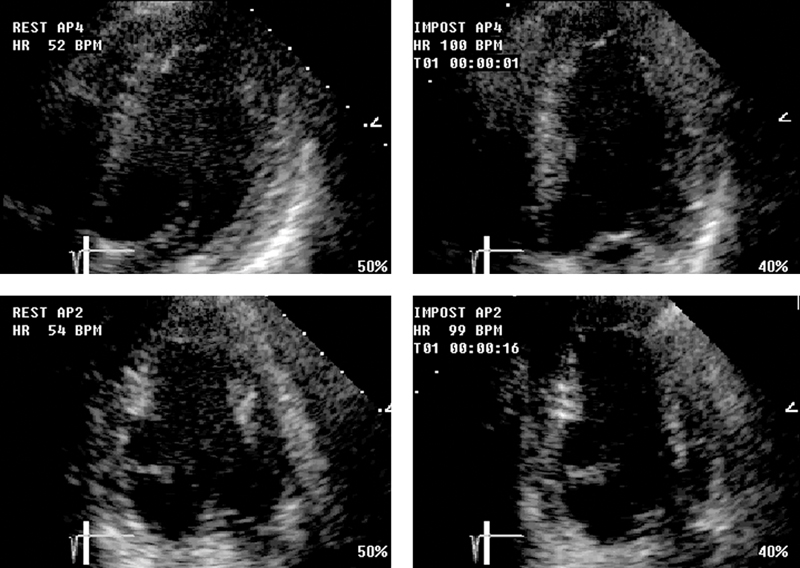

فحوصات تشخيصية لبعض امراض القلب والشرايين التاجية